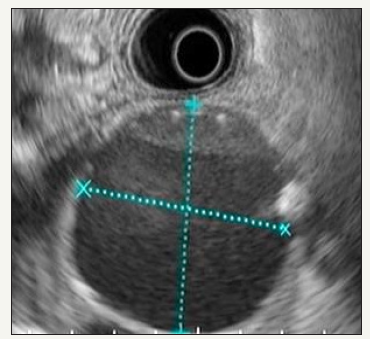

Figure 8A:EUS picture of MCN. EUS-FNA was performed: Amylase: 66MU/l, CEA: 391.8ng/ml, CA 19-9: 2000.00U/ml.

Figure 8: Clinical case of MCN in 47 years old woman.

The tumor is represented by a single cyst, with a thick fibrous outer capsule and thin internal septs [38] (Figure 8A & 8B). The MCN wall is lined from the inside with a single-layer prismatic epithelium containing mucin granules. The irregularity, nodules, cystic inclusions can be visualized on the inner surface of the capsule and septs [39,40]. It is important to remember that the presence of such nodules, especially those that accumulate contrast, can be a sign of malignancy. The contents of the cyst are mucinous, viscous, most often transparent, but may have hemorrhagic staining. The mucin staining is positive. The principal visual difference from IPMN is the absent of communication with the pancreatic ducts [12]. However, in some cases, the tumor can compress the pancreatic duct, causing its dilatation in the distal part [41]. A cyst is found more often in the body or tail of the pancreas [42,43]. According to current guidelines, all MCNs should be subjected to surgical resection if the patient who fit for surgery, especially tumors more than 4 cm and with sings of worrisome or high-risk criteria [2,44].